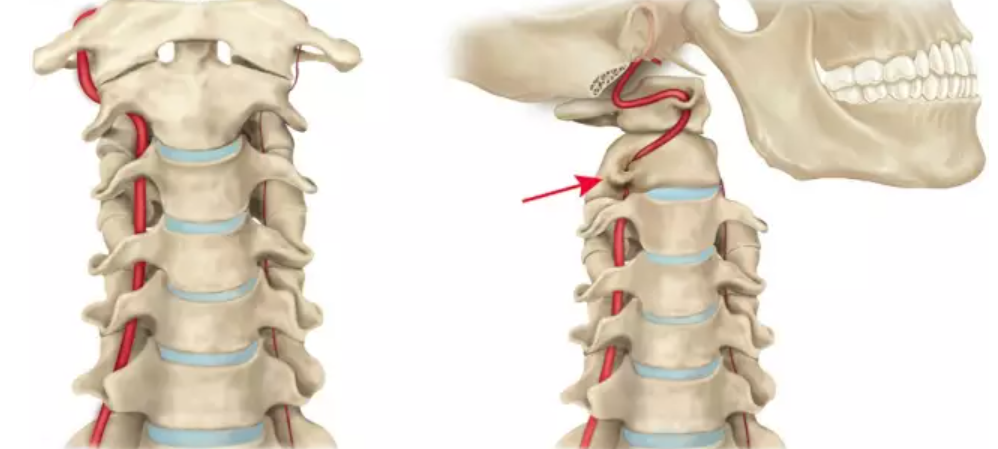

从影像学来看颈椎病为何会引起眩晕